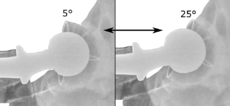

Acetabular anteversion.[79] This parameter is calculated on a lateral radiograph as the angle between the transverse plane and a line going through the (anterior and posterior) margins of the acetabular cup.[79]

Acetabular anteversion is normally between 5 and 25°.[7] An anteversion below or above this range increases the risk of dislocation.[7] There is an intra-individual variability in this method because the pelvis may be tilted in various degrees in relation to the transverse plane.[7]